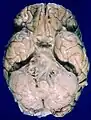

Human brain bottom view. Orbital gyri shown in green.